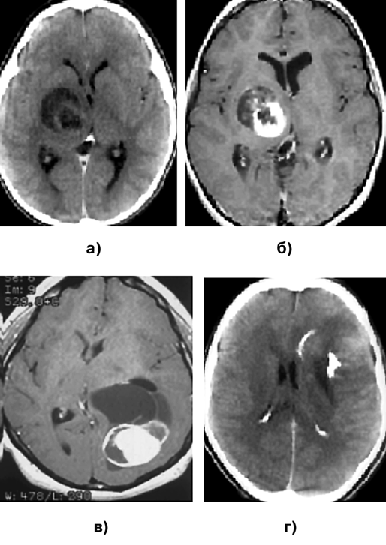

На КТ ПА обычно выглядят как округлые или овальные образования, хорошо отграниченные и имеющие гипо— или изоденсные характеристики (рис. 7а). В 10% всех ПА обнаруживаются петрификаты. Контрастное усиление носит вариабельный характер. Некоторые опухоли имеют сóлидное строение и контрастируются гомогенно, другие имеют пристеночный узел, накапливаюший контраст на фоне большой кисты. ПА, располагающиеся вблизи от 4 желудочка мозга, часто сопровождаются развитием обструктивной гидроцефалии.

На МРТ ПА выглядят как хорошо отграниченное объемное образование с макрокистами. В режиме Т1 ПА обычно имеют гипо— или изоинтенсивный сигнал, а на Т2-взвешенных изображениях опухоль чаще выглядит гиперинтенсивной. При введении препарата гадолиния отмечается интенсивное усиление сигнала от сóлидной части опухоли, в основном гетерогенного характера (рис. 7б).

Клиническая картина характеризуется длительно существующим эпилептическим синдромом. Рентгенологическая картина очень характерна: выявляется конвекситально расположенное, обычно в височной области, объемное образование, имеющее хорошо контрастируемую сóлидную часть и крупные кисты, при этом практически всегда отсутствуют признаки перитуморозного отека (рис. 7в).

Рисунок 7. Пилоидные астроцитомы:

а — ПА области подкорковых узлов справа (КТ с контрастным усилением, аксиальная проекция); б — ПА области подкорковых узлов справа (МРТ, Т1-взвешенные изображения с контрастным усилением); в — плеоморфная ксантоастроцитома теменно-затылочной области слева (МРТ, Т1-взвешенные изображения с контрастным усилением); г — олигодендроглиома заднелобно-височной области, распространяющейся на область подкорковых узлов слева (КТ с контрастным усилением)

Характерный рентгенологический признак — наличие петрификатов в опухоли, выявляемых при КТ в 90% наблюдений (рис. 7г). Ткань опухоли бывает гипо— или изо изоденсна по сравнению с окружающим мозгом. Контрастное вещество 2/3 ОДГ накапливают слабо. Редко выявляются кистозные или геморрагические изменения. Контрастное усиление, как и перитуморозный отек, характерны лишь для анапластических ОДГ.